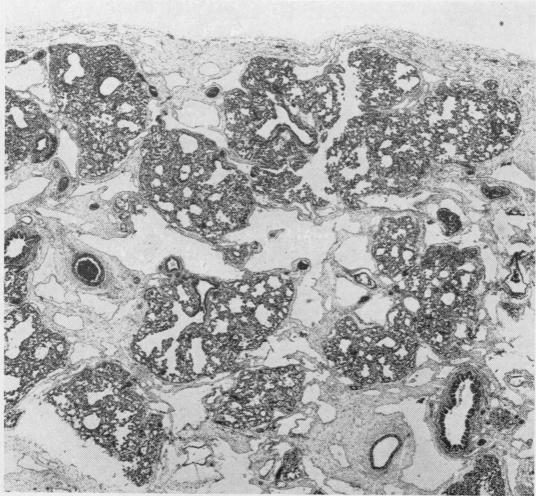

Congenital pulmonary lymphangiectasis.

J Clin Pathol. 1959 Jan;12(1):62-9. doi: 10.1136/jcp.12.1.62.